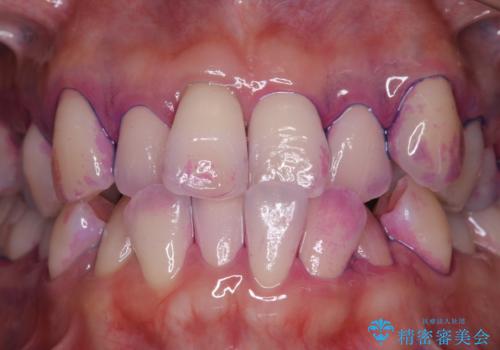

しかし、プラークは歯の色と似ているため、見ただけでは付着しているかどうかがハッキリとは分かりません。

染め出し液を使ってプラークを染め出すことにより、普段の歯みがきで磨き残している場所を目で確かめることができます。

日々の歯磨きを上達するには、まずどこが磨けていないか認識することが大切です。